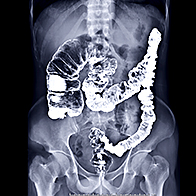

Colorectal cancer (CRC) is cancer of the colon or rectum. Abnormal growths called polyps can sometimes grow in these areas, potentially becoming cancerous, but not always. Colon cancer screenings can find these polyps so doctors can remove them before they turn into cancer.

The earlier you can be screened for cancer, the better. Colon cancer is the second-leading cancer killer in the United States among cancers that affect both men and women, according to the Centers for Disease Control and Prevention (CDC).